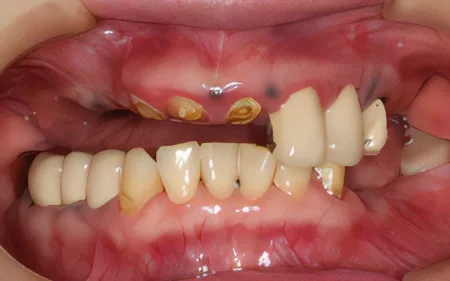

2024.08.1750代女性「歯科恐怖症で治療ができなかった。歯がボロボロで噛めない」インプラントとメタルボンドを入れ、物が噛めてご飯が食べられるようになった症例